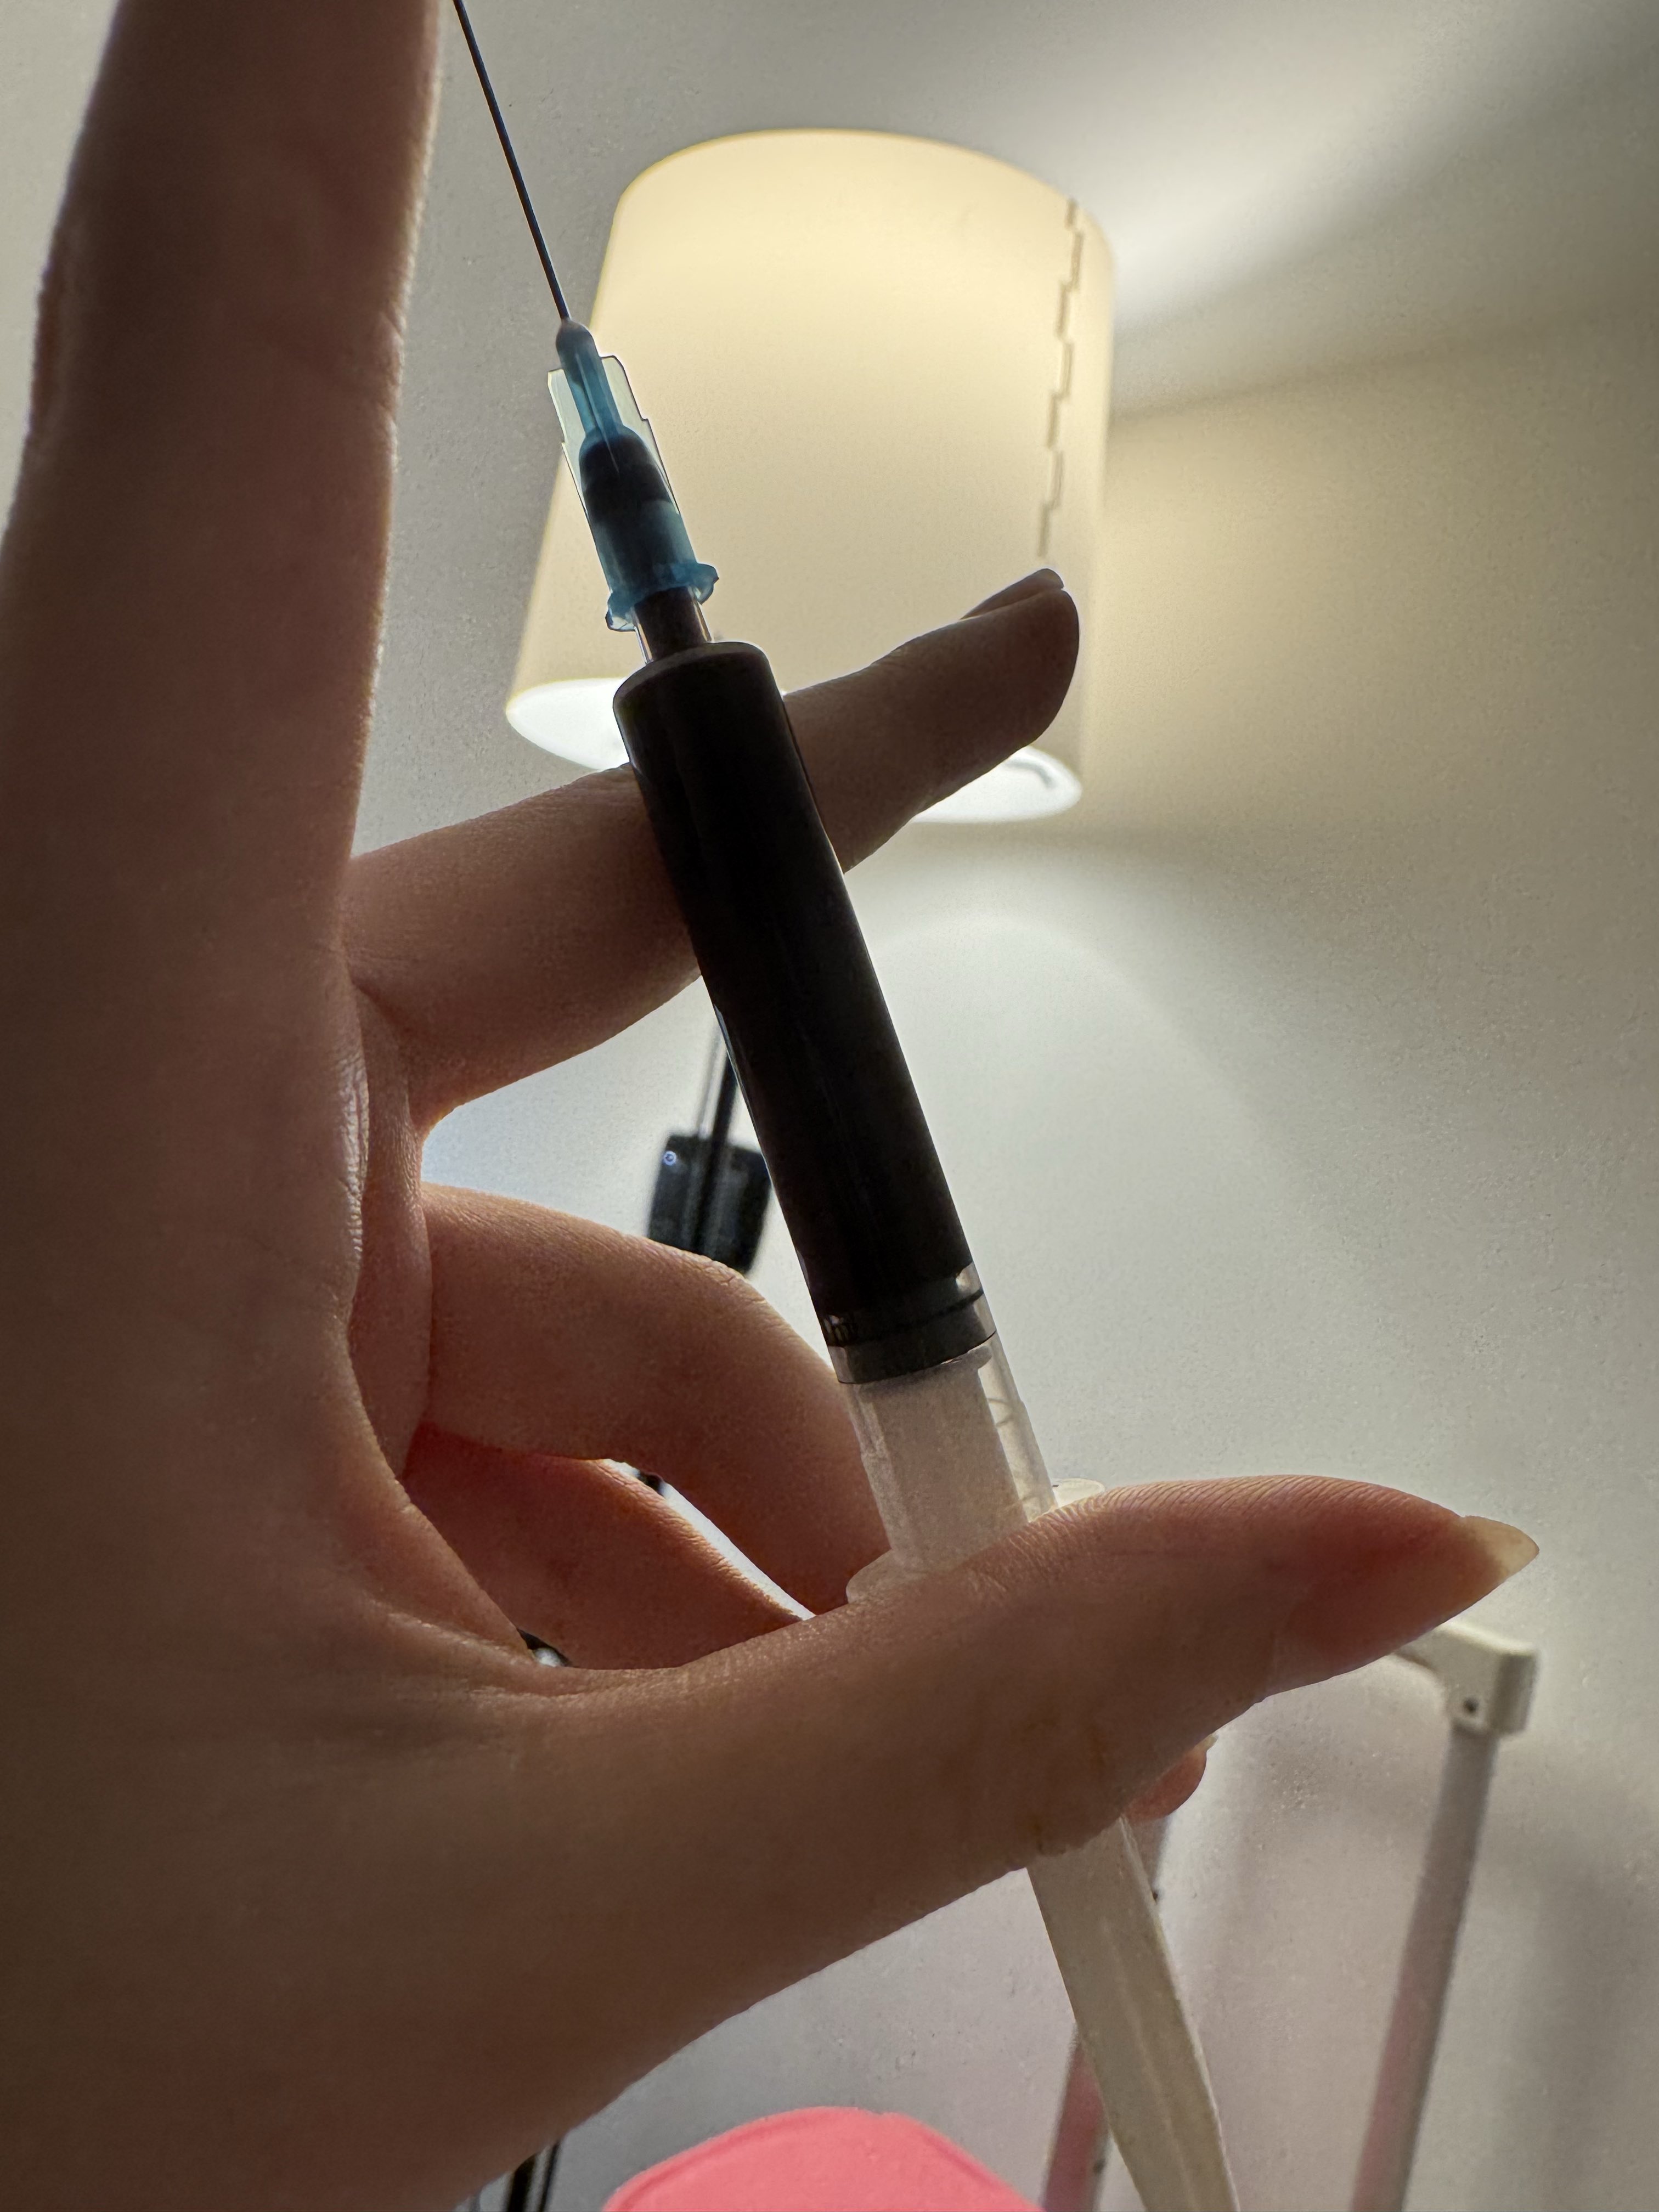

吃完唑吡坦会干一些难绷的事情,昨天睡不着疑似气急败坏了抽了0.5ml右美托咪定就是iv,还奇奇怪怪挑了个很痛的头静脉

后面不记得了,醒了灯开着的还以为是做梦,对着针孔一脸不可置信地整理记忆

你别说还扎得挺好的()按压时间估计也够,一点淤青也没有,不知道哪来的意志力 https://t.co/KxtfAUVSmb